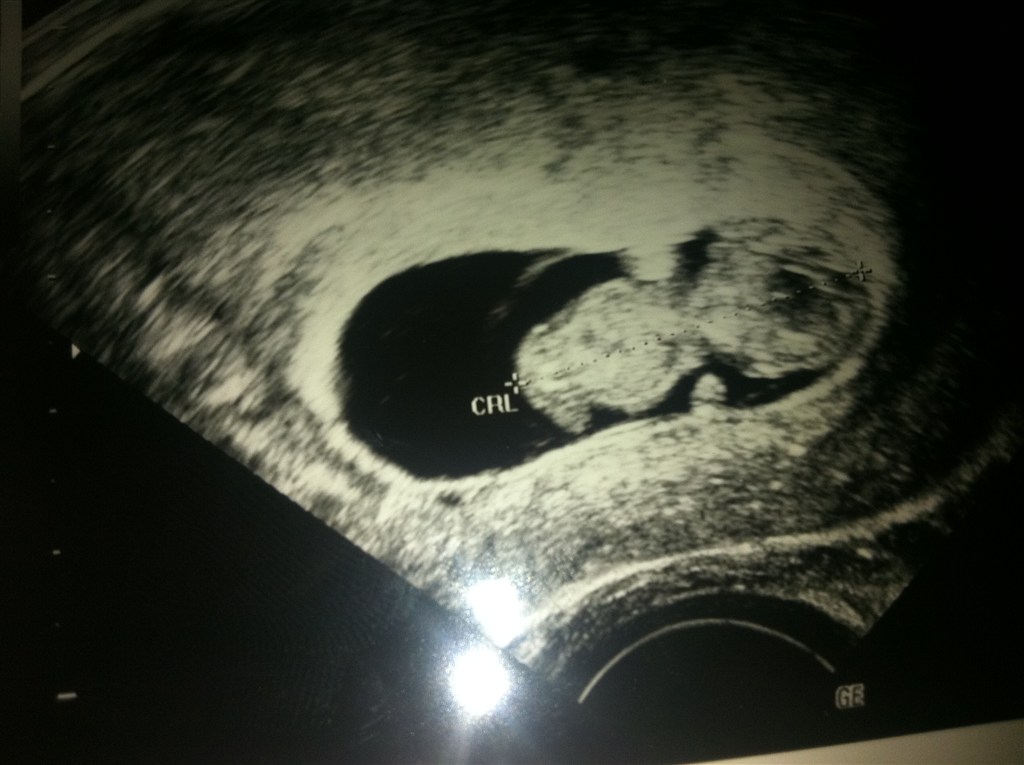

men har været til scanning og se vores baby idag, den var så aktiv og kunne se arme og ben og det hele den var så fiiin

Vedhæftede fotos (klik for at se i fuld størrelse)